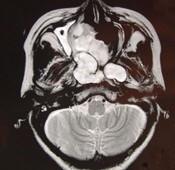

问题 女性,41岁,鼻腔流脓涕3年,鼻部面部肿胀1年,近来加重,MRI检查如图,请选择最可能诊断()

选项 A.鼻腔内囊肿 B.鼻腔内出血 C.鼻腔软骨瘤 D.鼻咽癌 E.鼻腔血管瘤

答案 C